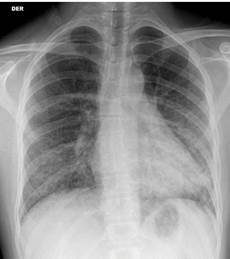

El paciente se controla con medico particular, quien indica estudio básico por sospecha de patología tiroidea; de manera incidental, en radiografía de tórax antero-posterior y lateral se pesquisa patrón de infiltrado bilateral intersticial, el cual es interpretado como neumonía atípica por patrón en la imagen y tos crónica. Los laboratorios son normales al inicio del cuadro clínico, por lo que se amplía estudio por sospecha de inmunosupresión y se inicia tratamiento con levofloxacino 500mg vía oral una vez al día por patrón dudoso de infiltrado bilateral (Figura 1).

Radiografía de tórax al ingreso que demuestra compromiso intersticial bilateral, de predominio perihiliar y basal mayor a izquierda y signos de vidrio esmerilado.

Figura 1: Radiografía de tórax al ingreso que demuestra compromiso intersticial bilateral, de predominio perihiliar y basal mayor a izquierda y signos de vidrio esmerilado.

Fuente: Documento obtenido durante la realización del estudio.

El sujeto es hospitalizado para tratamiento; al examen físico se evidencia enflaquecido, anictérico y afebril y al examen pulmonar se auscultan sibilancias espiratorias difusas, sin uso de musculatura accesoria, pero disneico y con apremio respiratorio pese a saturación de 98% ambiental. Durante la estancia, se recaba antecedente de al menos 3 meses de disfagia lógica con tos en acceso de predominio nocturno asociado a baja de peso. Dentro de la historia destaca antecedente de relación homosexual de larga data sin protección y sin conocimiento de serología de su pareja. Al analizar la radiografía, el patrón radiológico evidencia neumonía por Pneumocystis jirovecci (Figura 1), por lo que se decide ampliar estudio serológico para VIH, sífilis y virus hepatotropos, destacando positivo para citomegalovirus (Tabla 2).